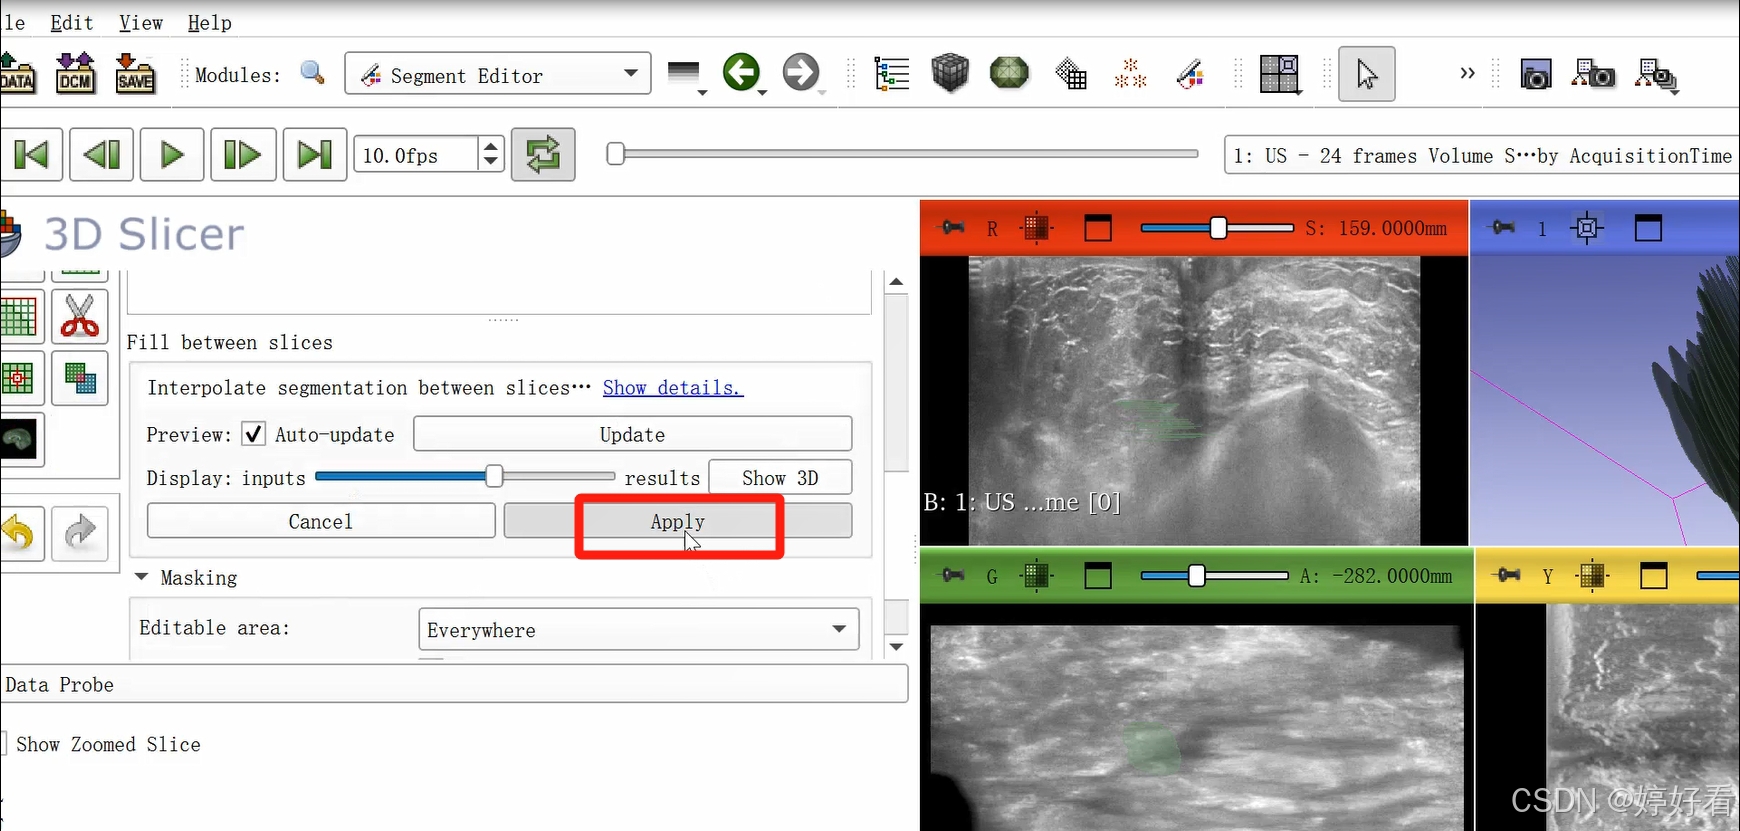

2.6 使用Fill between slices功能

上一步中完成的三维图像不是完整连续的三维图像,是一层一层的。Fill between slices这个功能可以自动填充每一层之间的间隙。选中Fill between slices,然后依次点击Initialize-Apply。